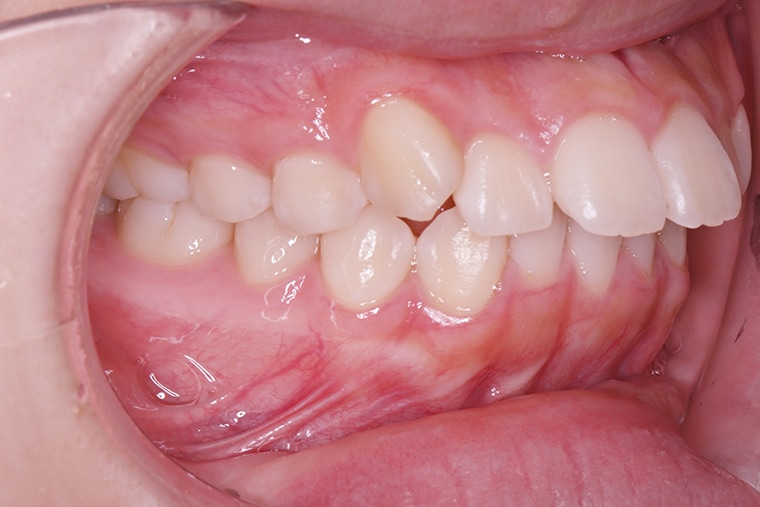

Case Study15歳女性出っ歯のマウスピース矯正-矯正期間10ヶ月

BEFORE